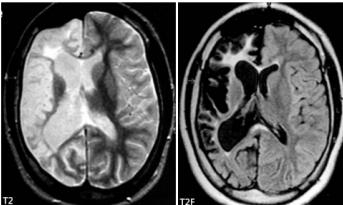

Rasmussen脑炎

Rasmussen脑炎是一种不明原因的慢性、进行性脑炎,一般多累及一侧大脑半球,或虽表现为两侧大脑受累但以一侧半球萎缩显著。

多发生于儿童,成人发病少见。

临床表现主要为局灶性难治性癫痫、部分性癫痫持续状态、进行性神经功能缺损(偏瘫、偏盲、智力下降等)。

颅脑MRI表现:一侧大脑半球萎缩性改变(脑室扩大、外侧裂和脑沟增宽、脑回变小),伴有相应部位的灰质或白质萎缩和T2WI、FLAIR高信号,深部灰质核团(尾状核和壳核)也可受累,无颅骨代偿性改变。少数早期患者可表现为暂时性局部皮质肿胀及T2WI、FLAIR高信号。